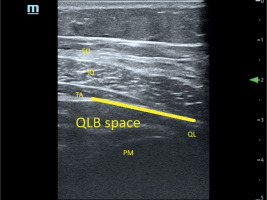

Patients were placed in the lateral decubitus position. After skin disinfection, a linear high-frequency (L14–6NS) ultrasound probe (Mindray, UMT-400 Mindray Building, Nanshan, Shenzhen, People’s Republic of China) guarded with a sterile cover was set above the iliac crest and shifted cranially until the three abdominal wall muscles were distinguished. Then, it was moved medially until the latissimus dorsi and quadratus lumborum muscles (QLM) were shown within identical short-axis views. A 21-gauge needle (Echoplex+ REF 6194.853, 85 mm) was inserted from the edge of the probe using an in-plane technique and advanced into the fascia over the QLM. After ensuring negative aspiration for blood, 30 mL of 0.35% ropivacaine was injected slowly into the fascial interspace between the QLM and internal oblique muscles (Figure 2). An experienced anesthesiologist performed this procedure bilaterally on each patient.

FIGURE 2

Ultrasound image of the approach to quadratus lumborum block (QLB). The line shows spaces where local anesthetic spread from the posterior layer of the thoracolumbar fascia on the quadratus lumborum (QL) muscle. TA – transversus abdominis muscle, IO – internal oblique muscle, EO – external oblique muscle, PM – psoas major muscle